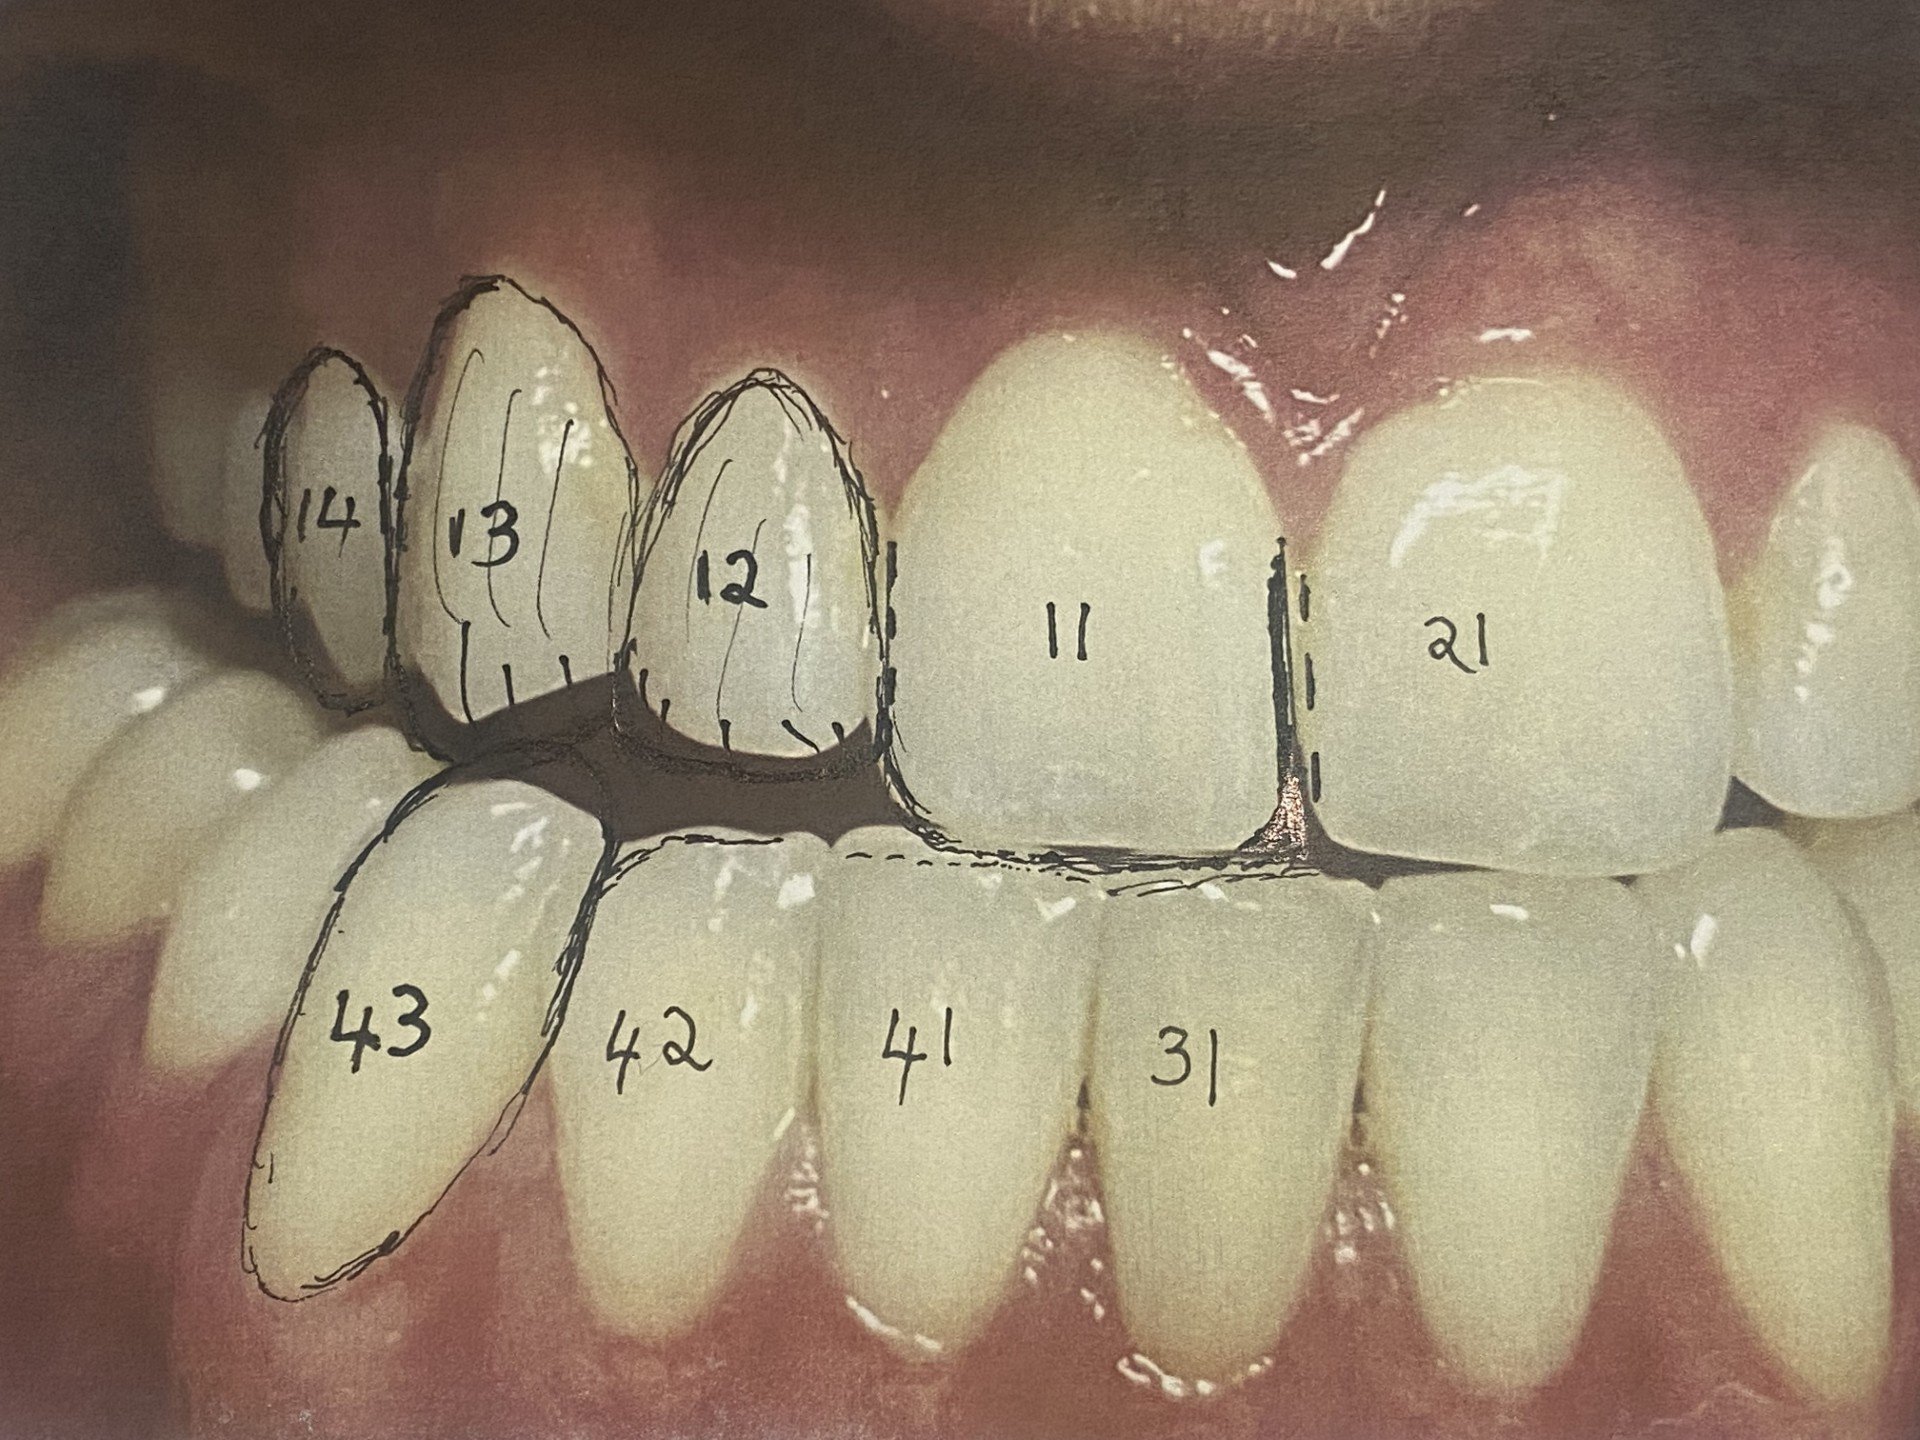

Here we see how the lower 43 canine is not only short in stature but rotated in towards the tongue.

Line diagrams are necessary to address the dental asymmetry, upper dental midline and the bio-designing of right protective bite. This involved drilling the midline between the 11 and 21 teeth towards the left hand side and placing a filling on the mesial surface of the 11 tooth. Narrowing the distal surface of the 11 tooth to equalise the widths of the front 11 and 21 teeth. Overlaying of the 12 tooth onto the distal surface of the 11 and bringing it forward into the arch and longer was required. Similarly, overlaying the 13 and 14 was performed. The lower right 42 lateral incisor was narrowed on the distal surface to fit the lower right 43 canine temporary crown. The biting edges of the 31, 41 and 42 were adjusted to create a protective bilateral balanced forward bite with the upper front 11 and 21 teeth.